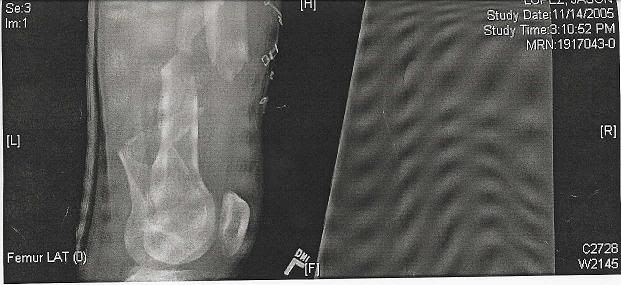

I was in a motorcycle accident 15 months ago.

Injuries:

Compound fracture of my femur - bone shot through my leather suit, split the knuckle on the femur in the knee in half

Shattered my forearm/humerus

Ripped my arm off of my body and was held on by the skin only - all nerves were severed, rendering the arm useless

Tore the brachial artery into my arm - required 16bags of blood (2 full transfusions) over 12 hrs. - died of blood loss and had to be revived

Cracked scapula

Fractured 4 vertebrae

Collapsed lung

Concussion

http://i12.photobucket.com/albums/a219/jdoggg1/kneeside.jpg